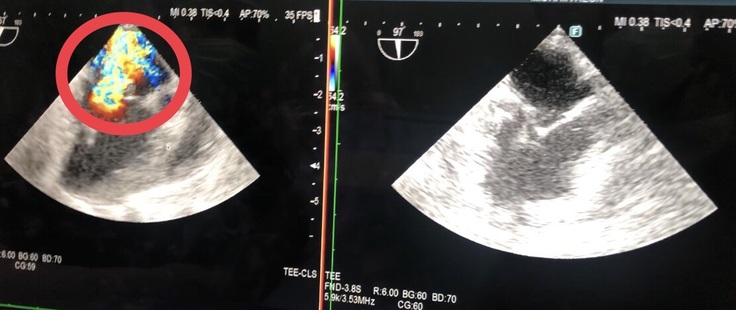

かなり分かりづらいと思いますが、写真の

【左】手術前のかなり変形して切れてしまっているレオンの僧帽弁

【右】手術で先生に修復してもらった後のレオンの僧帽弁 です。

また、写真の

【左】虹色になっている部分が手術前に逆流をしてしまっていた血液です。

【右】右側にもまだ多少逆流はありましたが、左側ほどはっきりしたものではなく、徐々になくなるか、生活に支障がない程度になるとのこと。